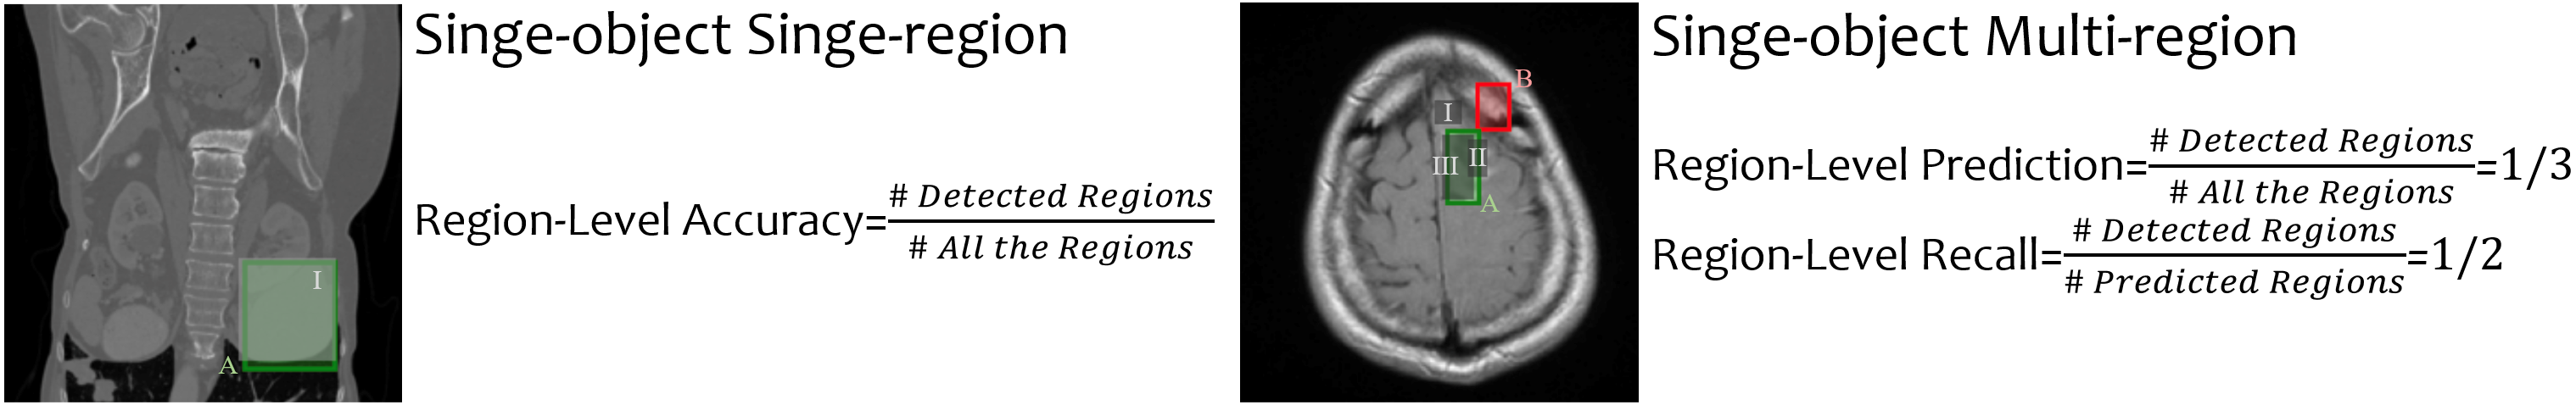

Settings. In the Text-to-Region Detection task, the model should detect the region corresponding to specific organs or anomalies. The input textual instruction contains the name of single or multiple objects, and the model is expected to output bounding boxes for all the relevant regions. We classify the task into four categories according to the number of detected objects and the number of regions per object: single-object single-region, single-object multi-region, multi-object single-region, and multi-object multi-region, as illustrated in Appendix A.1.1. We evaluate the performance across three dimensions: (1) Object-Level: assessing the correctly identified objects; (2) Region-Level: assessing accurately detected regions; (3) Object-Region Alignment: assessing whether the detected boxes are correctly aligned with the corresponding object. For single-object detection, all the output boxes are aligned with the given object, where evaluating the detection performance from the region-level is sufficient. The region is correctly detected if its Intersection over Union (IoU) score exceeds the threshold of 0.5. For multi-object detection, the alignment of text and box must also be considered. Figure 6 illustrates the three-dimensional evaluation in the multi-object setting.